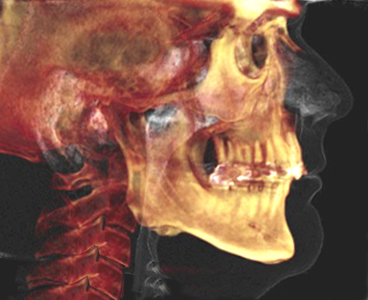

Computed tomography (CT) uses a narrowly collimated beam of x-rays that rotates in a full arc around the patient to produce an image of detailed cross-secional slices. A major advantage of CT is its ability to image bone, soft tissue and blood vessels all at the same time. An array of detectors, positioned at several angles, records those x-rays that pass through the body. The image is created by a computer that calculates tissue absorption and can produce three dimensional reconstructed images representing tissues that demonstrates the densities of the various structures. CT is less sensitive to patient movement than MRI. CT can be performed if you have an implant medical device of any kind, unlike MRI.

Tumor masses, infarctions, bone displacement, and accumulations of fluid may be detected. It is useful for the diagnosis of bony abnormalities including fractures, dislocations, arthritides, ankylosis, and neoplasia. Three dimensional reconstructed images can be produced.